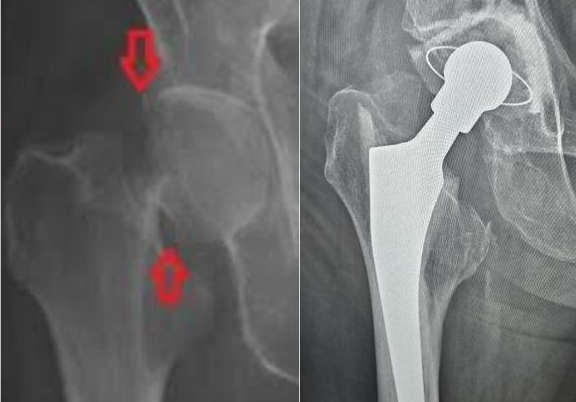

Пожилые люди находятся в зоне высокого риска по переломам из-за снижения плотности костной ткани и уменьшения мышечной массы, что может привести к нарушению баланса и повышенному риску падений. Для пациентов этой возрастной группы перелом шейки бедра — реальная угроза жизни. Раньше каждый второй из тех, кто сталкивался с такой травмой, терял самостоятельность и нуждался в уходе. Сейчас благодаря эндопротезированию тазобедренных суставов после оперативного лечения пациенты снова могут ходить. Однако лучше опасность предупредить, чем устранять её последствия, тем более, что в ряде случаев операция может быть противопоказана.